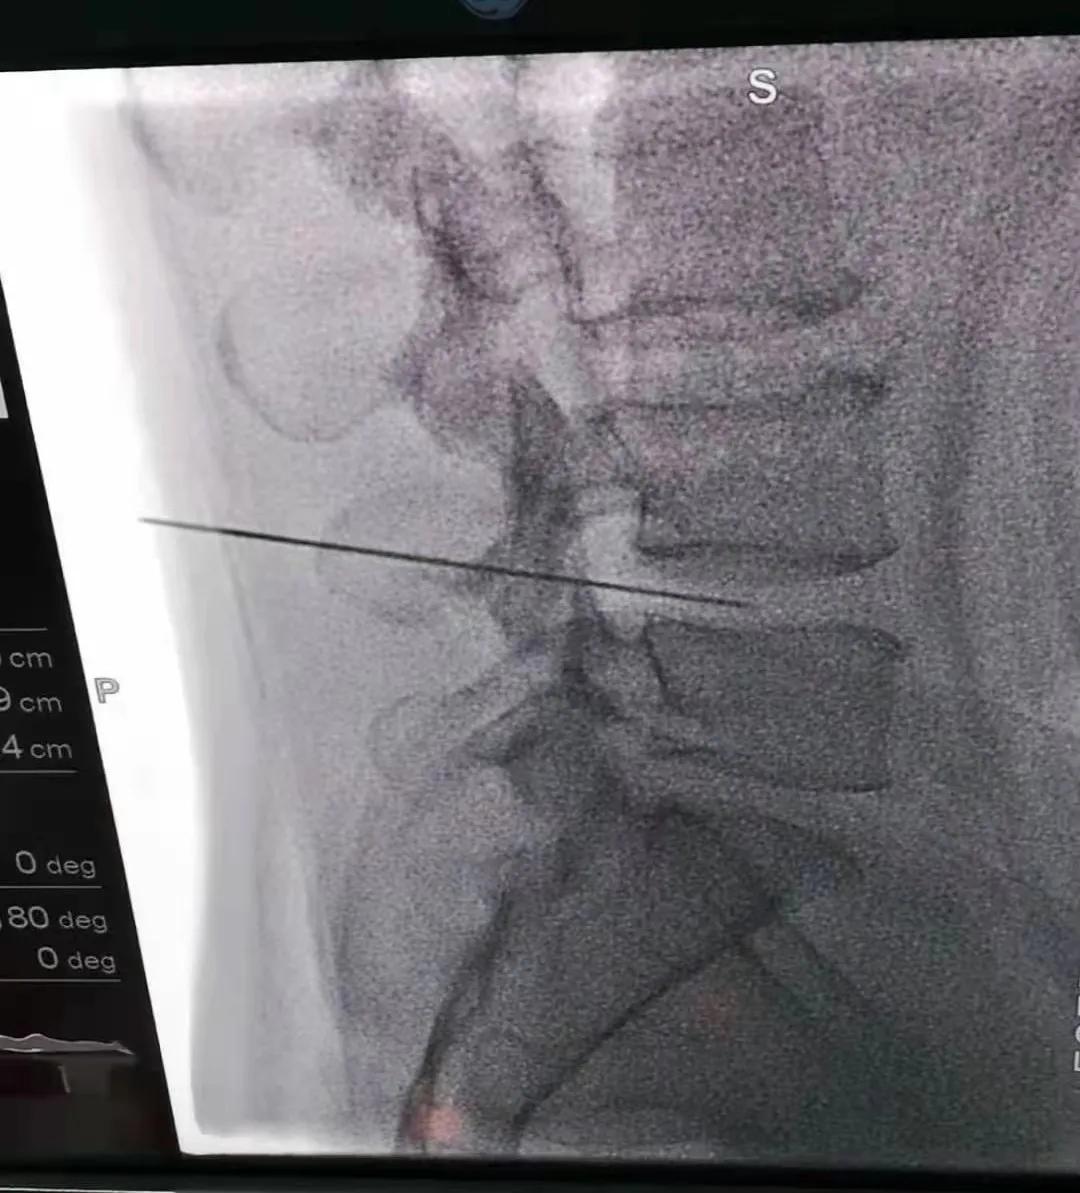

随着超声技术的进步,越来越多的临床医生运用超声技术解决临床问题,对于我们疼痛科医生来说, 可视化超声引导无疑是为我们以前凭经验、凭感觉穿刺送来了光明。

医师能够通过超声成像技术直接观察神经及周围的结构,在实时的超声引导下精确定位靶向治疗目标,同时,超声能够清晰的显示外周神经及其主要分支的走形及结构,这就使超声引导下的神经阻滞治疗能够做到高度特异性和选择性,实施 精准的神经阻滞,减少对周围组织的损伤。

还可通过超声观察局麻药的注射过程,从而保证局麻药均匀的扩散到神经周围,阻滞效果更加确切,同时也极大地减少了并发症的发生,成为了医生的“第三只眼睛”。如果说采用传统解剖定位方法神经阻滞是盲人在探路的话,而超声引导穿刺技术是真正赐予了这位盲人明亮的双眼。

6.超声引导下颈、胸、腰脊神经后内侧支阻滞术:用于项部及胸背部疼痛的治疗。